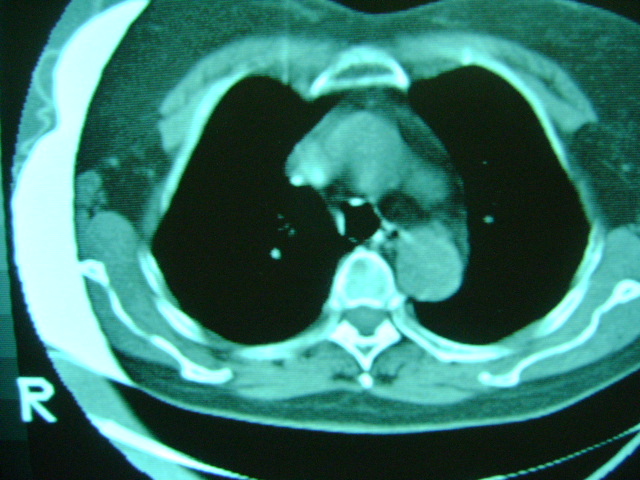

朋友的母亲,56y,咳嗽三个月,感觉左肺门不对,请大家给点意见

左肺门还可以吧

左肺门未见异常!